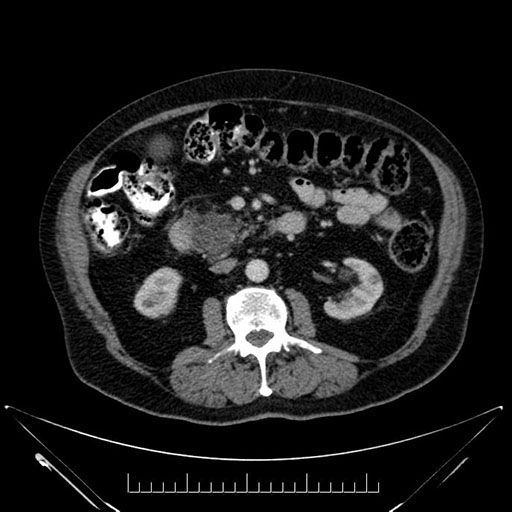

Imaging Analysis

Look through the patient's CT scan to identify any areas of concern for the necessary procedure.

Based on your CT findings, which issue(s) would give reason for "planned slowing down moment(s)" in this case?